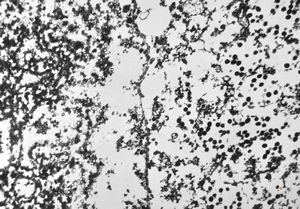

staphylococcal bacteriophage